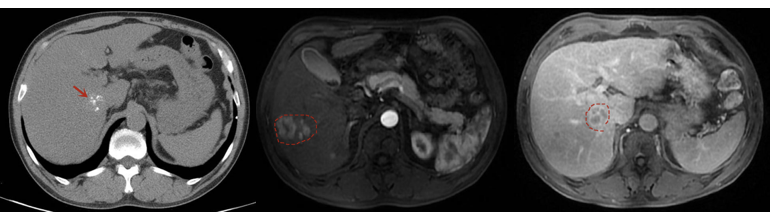

但至第1次TACE术后约15个月时间(2021年6月15日),复查发现肝内肿瘤明显进展(图5);AFP明显升高:6231.00 ng/mL。此时更换方案为二线靶向药物瑞戈非尼,160mg,qd,3周方案。同时联合免疫治疗:卡瑞利珠单抗200mg,静脉点滴,每3周1次。

图5.2021年6月15日上腹部CE-MRI

更换方案后1个月(2021年7月20日),肝内肿瘤病灶仍持续进展(图6),AFP升高至10795.00ng/mL。

图6.2021年7月20日上腹部CE-MRI

术后17个月左右(2021年8月27日),上腹部CE-MRI:肝内肿瘤病灶明显消退(图7)。AFP降至92.89ng/mL。

图7.2021年8月27日上腹部CE-MRI

2022年4月27日,术后2年余复查上腹部CE-MRI:肝内肿瘤病灶继续消退,无明显活性,无新发肿瘤病灶(图8);AFP降至正常范围内2.19ng/ml。按照mRECIST标准基本达到完全缓解(CR)。

图7.2022年4月27日上腹部CE-MRI